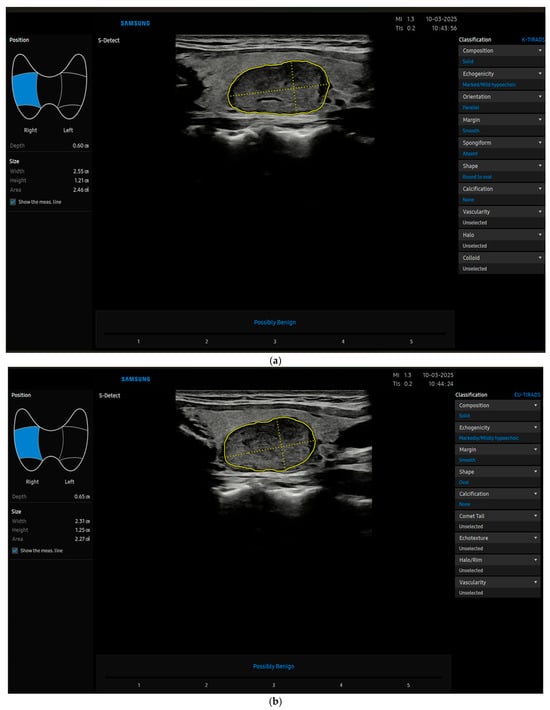

Recently, radiomics is taking its place in thyroid imaging and beyond; it uses extraction algorithms to derive various quantitative features from radiological images, and can be used by machine learning (ML) systems, which is a subset of artificial intelligence (AI) from which deep learning (DL) is derived. These innovative technologies may eventually translate into software used directly by clinicians, namely computer-aided diagnosis (CAD) [10,11] (Figure 1a–c), which is a type of deep learning software.

Figure 1.

(a) The image shows a thyroid nodule characterized by CAD (S-Detect) as benign (later confirmed cytologically and by follow-up) by using K-TIRADS. (b) The image shows the same thyroid nodule characterized by CAD (S-Detect) as benign by using EU-TIRADS (later confirmed cytologically and by follow-up). (c) The image shows the same thyroid nodule characterized by CAD (S-Detect) as benign by using ACR-TIRADS (later confirmed cytologically and by follow-up).